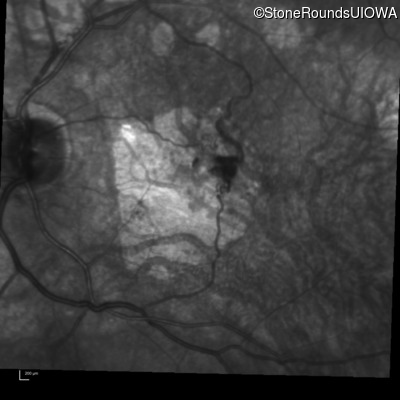

Fluorescein Angiography - Left - 20/40 sc

Exemplar